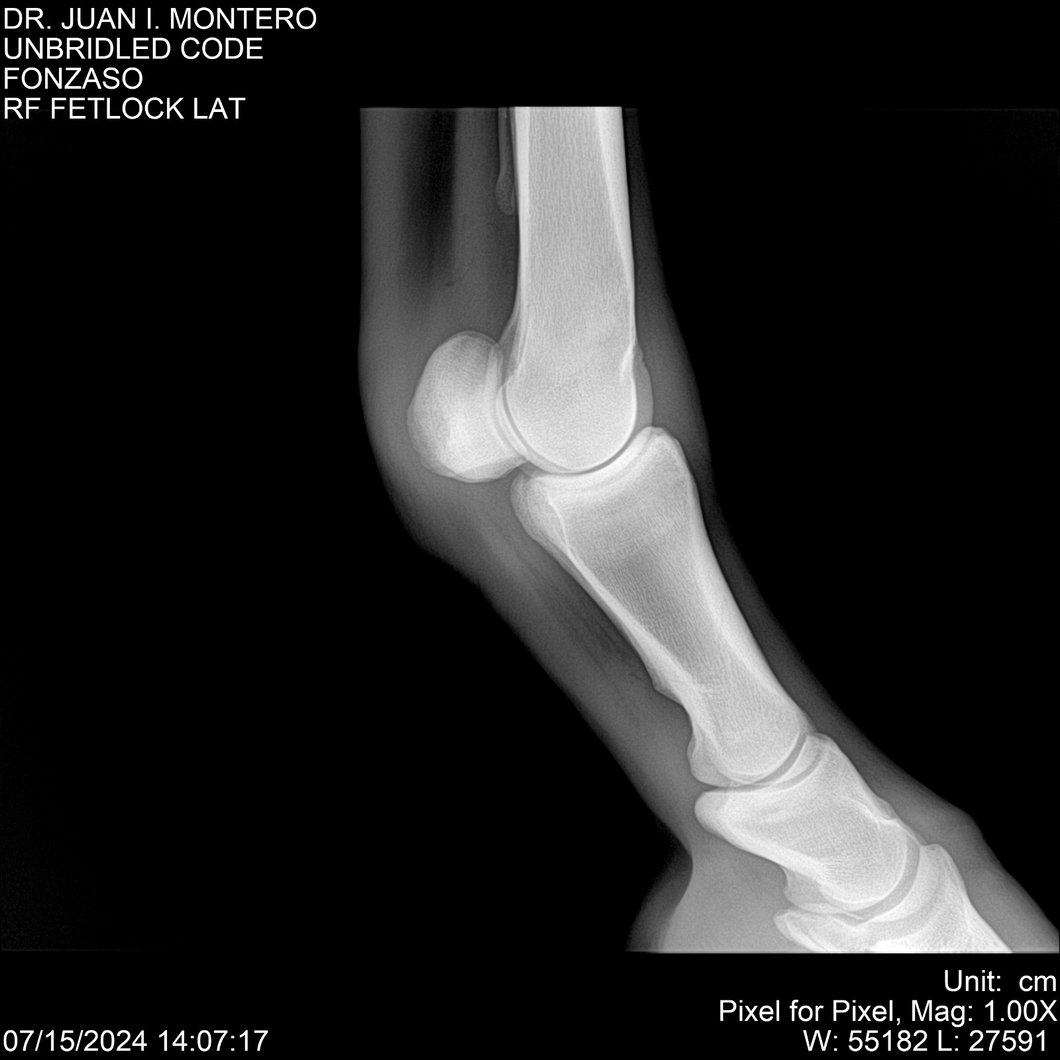

• Empresa: Abelenda N. R., Walter Hugo